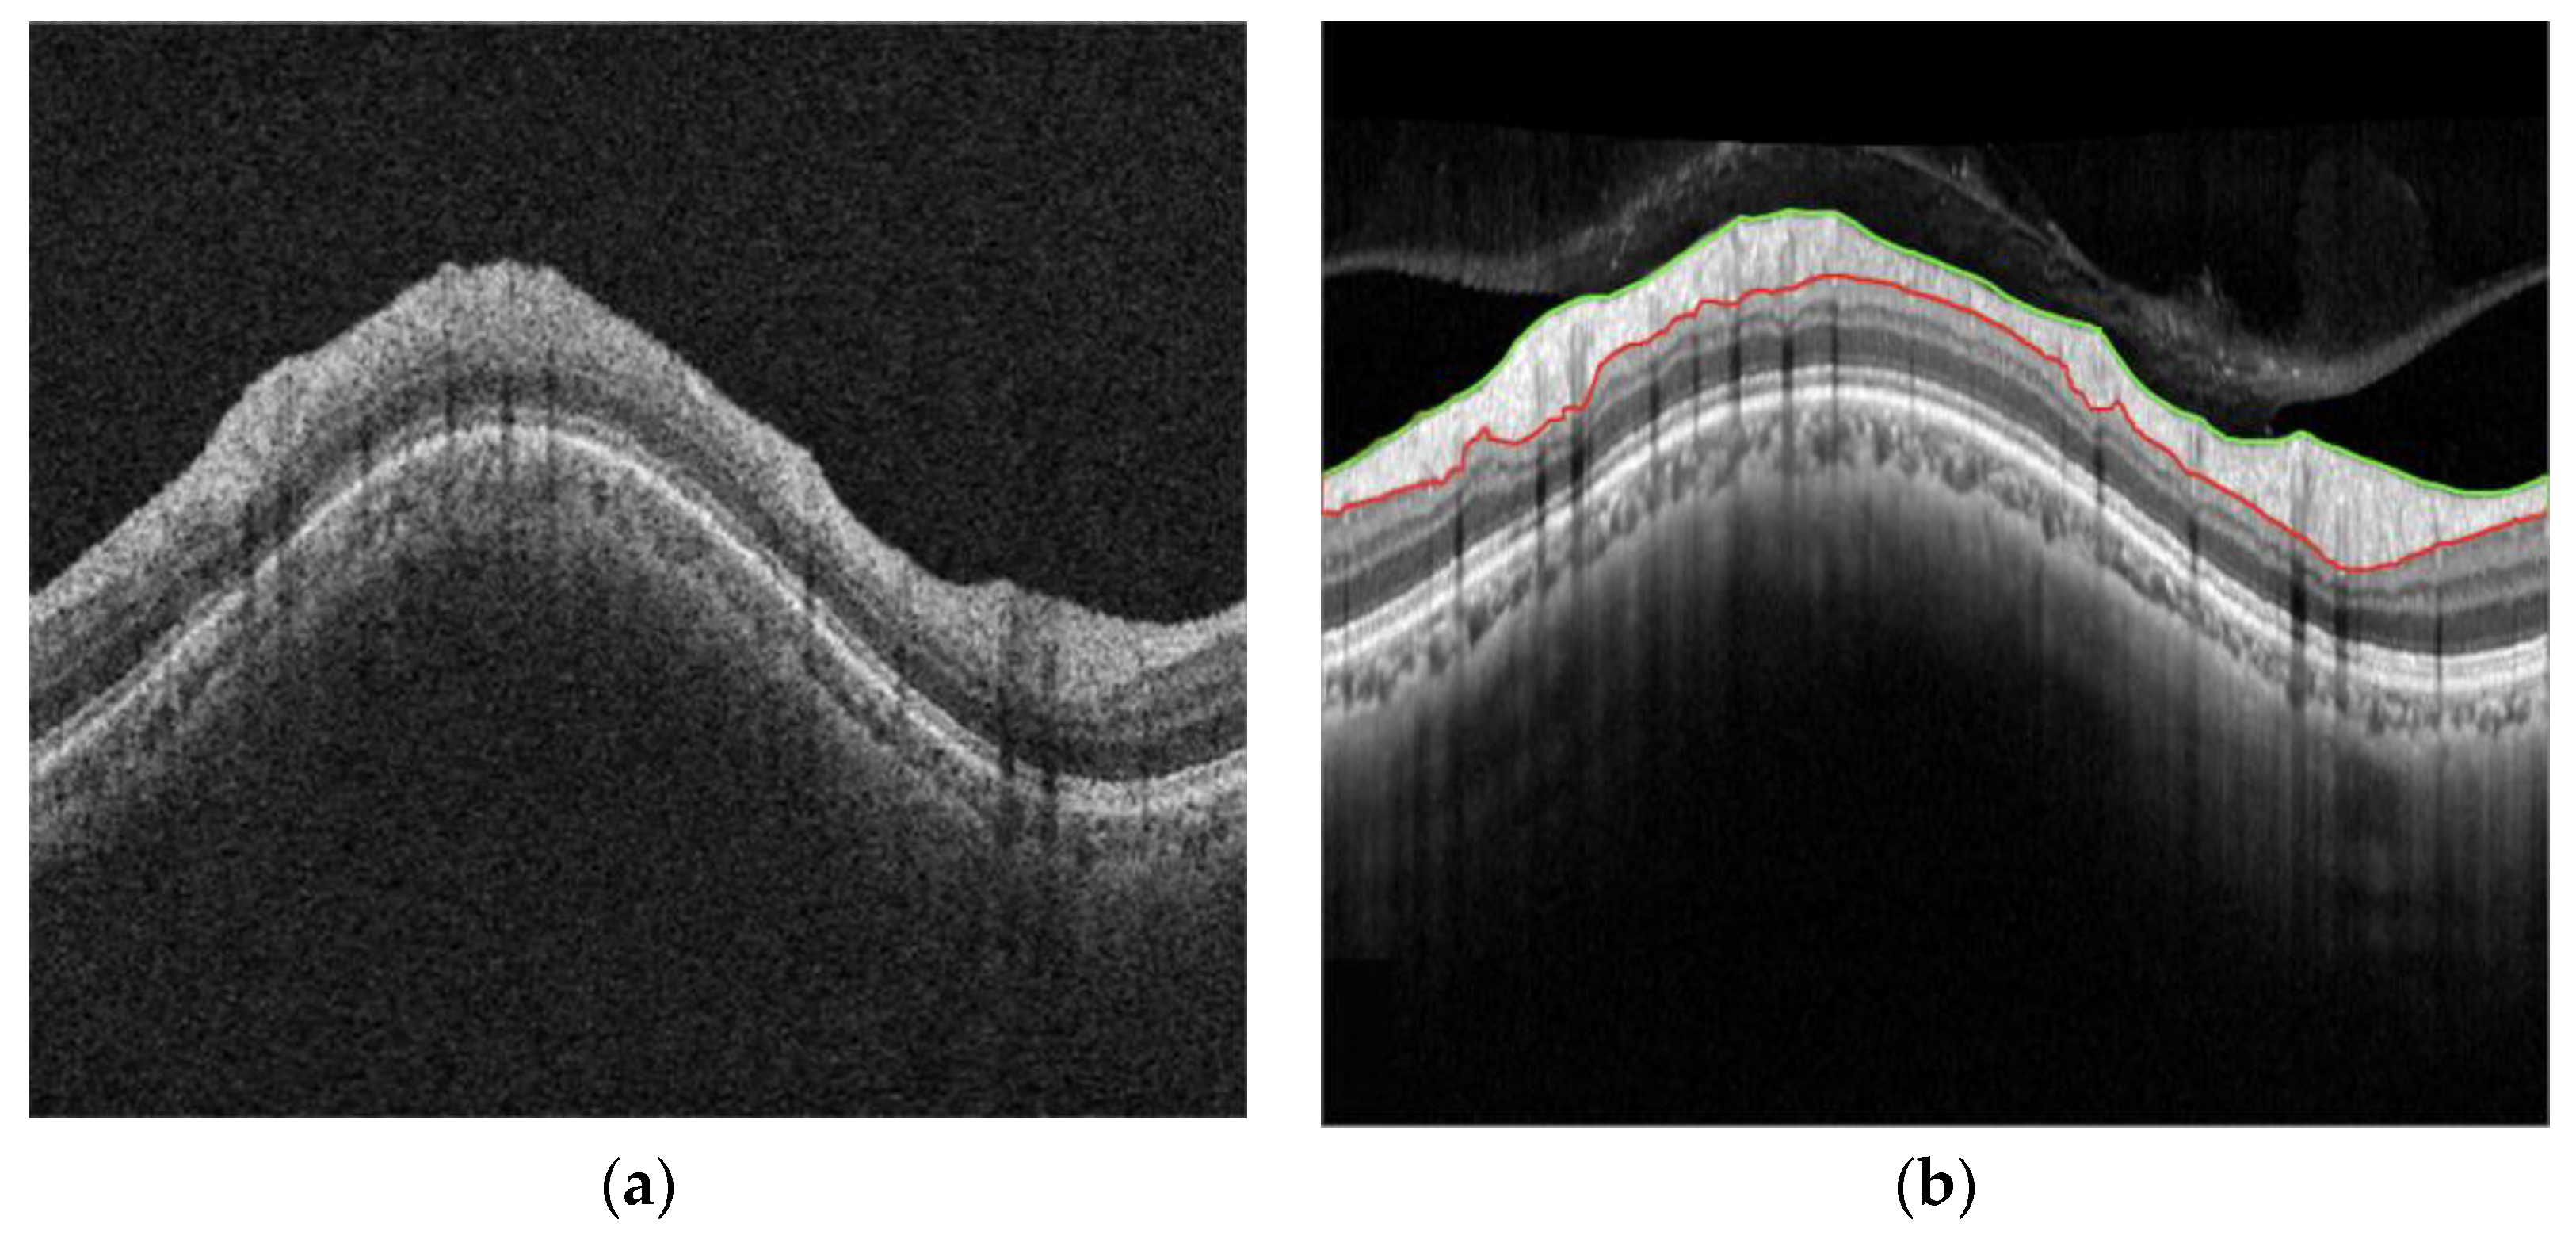

2. Materials and Methods

Figure 1. Four types of image datasets. (a) A-raw; (b) A-curve; (c) B-raw; (d) B-curve. The colored lines are the manual segmentation lines by clinical experts.